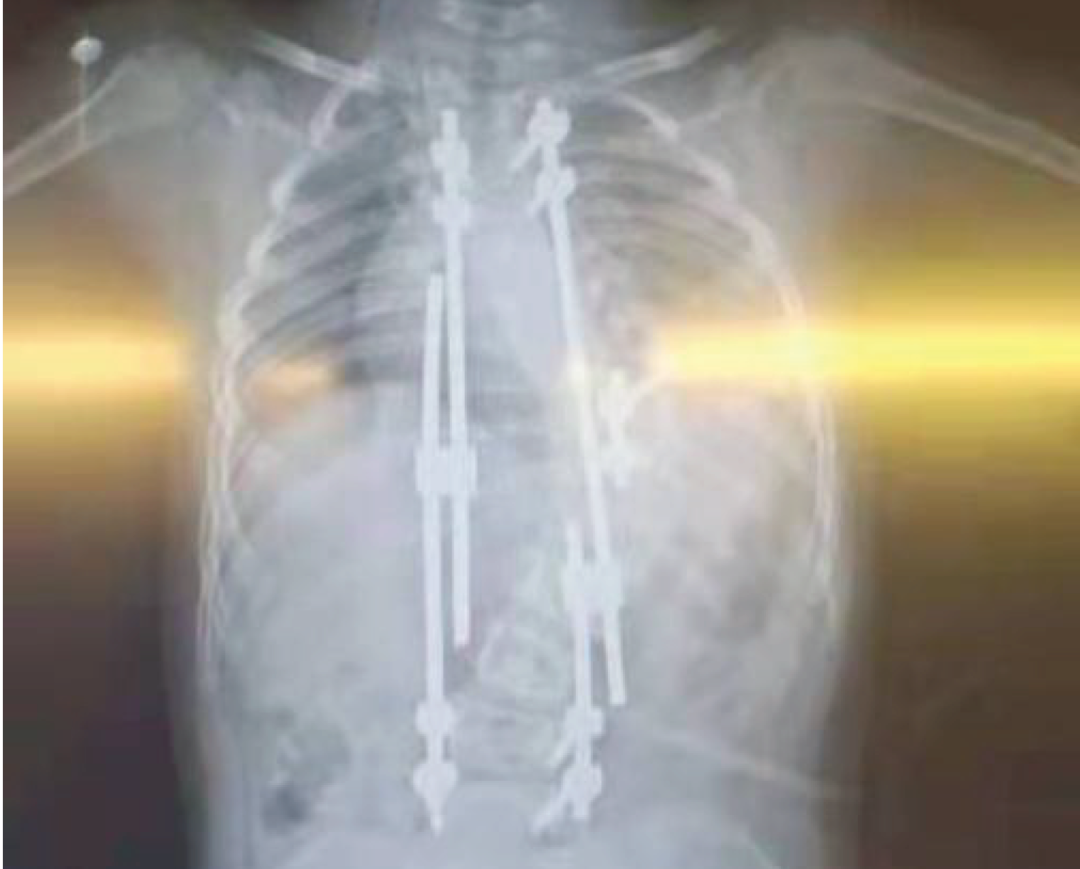

脊柱矯形術(shù)后效果

德康醫(yī)療——脊柱畸形去旋轉(zhuǎn)類方案

北京協(xié)和醫(yī)院仉建國(guó)教授團(tuán)隊(duì)合作研發(fā)的VSS脊柱專用矯形器械,功能強(qiáng)大,靈活應(yīng)對(duì)脊柱復(fù)雜三維矯形手術(shù)。

VSS惟德矯形系統(tǒng)器械常搭配單平面螺釘用于脊柱旋轉(zhuǎn)畸形患者的去旋轉(zhuǎn)操作 VSS惟德矯形系統(tǒng)器械分5.5系統(tǒng)和6.0系統(tǒng)